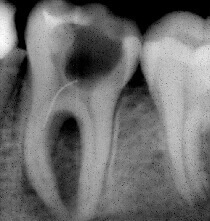

Проблема. Глубокая кариозная полость

Решение. Каналы были очищены, подготовлены к пломбированию, сделан дентальный снимок с пломбировочным материалом.

Запломбированы корневые каналы зуба. Зуб подготовлен к дальнейшему лечению.